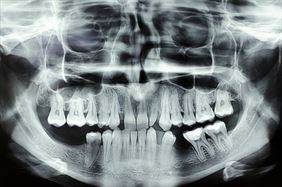

Rentgenodiagnostyka stomatologiczna odgrywa kluczową rolę w precyzyjnej ocenie stanu zdrowia zębów, kości szczęki, żuchwy oraz zatok szczękowych. Dzięki obrazowaniu radiologicznemu możemy wykryć zmiany niewidoczne gołym okiem, takie jak próchnica pod wypełnieniami, ubytki strukturalne, stany zapalne czy torbiele. Zdjęcia rentgenowskie są również niezbędne przy planowaniu leczenia ortodontycznego, implantologicznego oraz chirurgicznego.

W naszym gabinecie wykonujemy różne rodzaje zdjęć RTG, w tym:

• zdjęcia panoramiczne,

• zdjęcia punktowe,

• zdjęcia cefalometryczne.

Nasz sprzęt pozwala nam na uzyskanie obrazów o wysokiej rozdzielczości przy jednoczesnym minimalizowaniu dawki promieniowania. Zdjęcia wykonujemy zarówno w formie analogowej, drukowane na kliszy, jak i w wersji cyfrowej, zapisanej na płycie CD. Dzięki temu pacjenci mogą łatwo przechowywać i udostępniać wyniki badań lekarzom prowadzącym.

Dbamy o to, aby każde badanie przebiegało sprawnie i komfortowo. Aparat dostosowuje się do pacjenta, co zapewnia wygodę podczas wykonywania zdjęcia i precyzyjne dopasowanie parametrów ekspozycji.